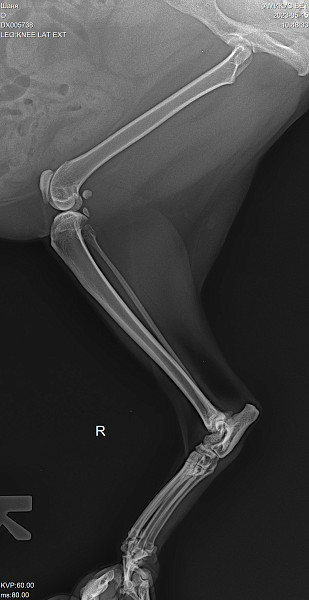

Лечение суставов у кошки

Лечение суставов у кошки 111 фотографий